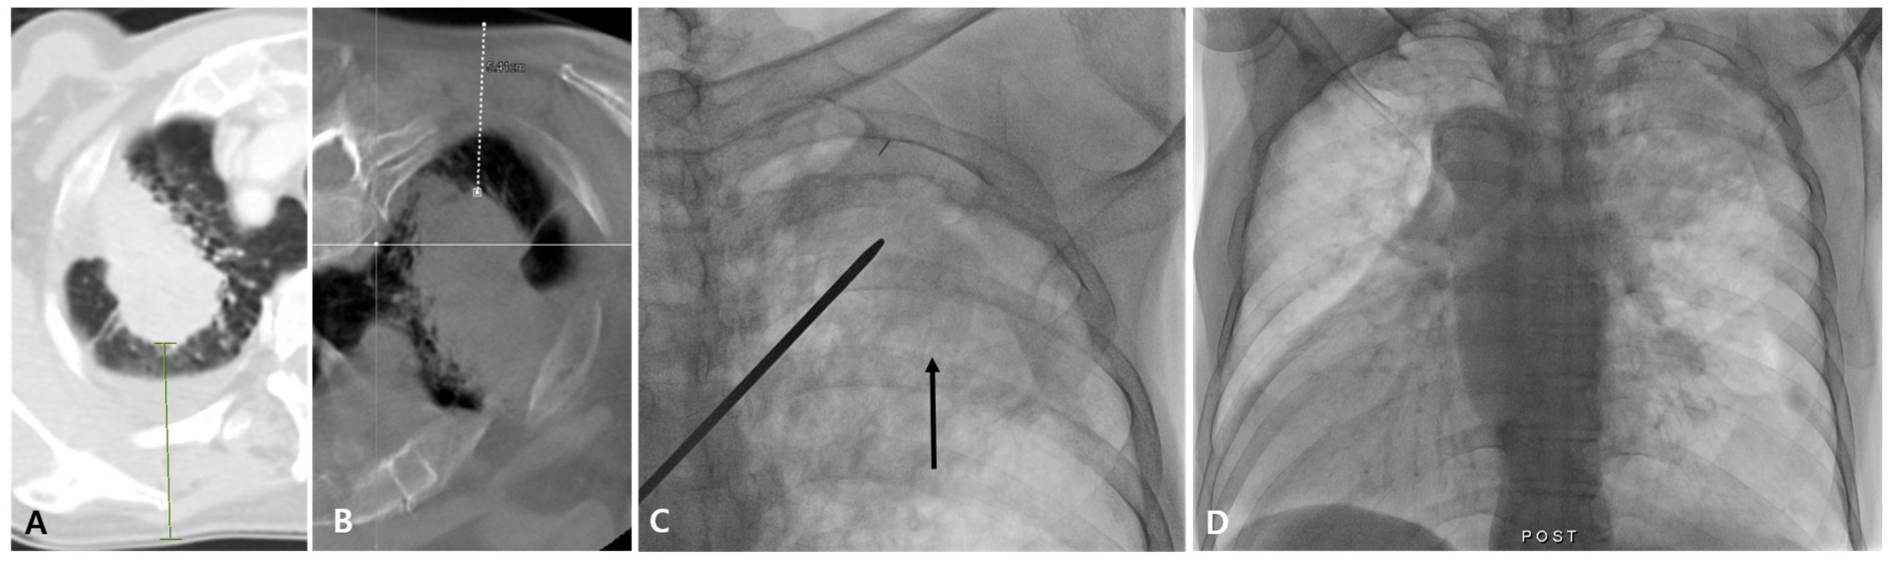

Figure 3.

A >10 mm difference in the lung nodule lesion depth was observed via fluoroscopy-guided PTNB with the aid of planning CBCT in a 75-year-old man with lung adenocarcinoma. A diagnostic CT image (A) shows a 69 mm lesion depth (green line), and a planning CBCT image in the prone position with scapular lateral rearrangement (B) shows a 54 mm lesion depth (white dashed line) for a 70 mm mass in the left apex. On fluoroscopy, the mass is identifiable (arrow) (C), and PTNB was performed based on the 54 mm lesion depth observed via CBCT. After PTNB, no immediate PTNB-related complications occurred (D), and diagnostic success was achieved.